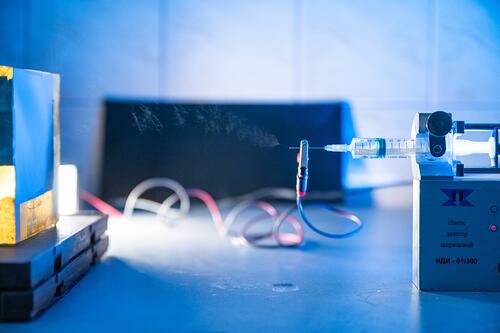

НИТУ «МИСиС» совместно с НИЦ эпидемиологии и микробиологии имени Н.Ф. Гамалеи приступили к испытаниям in vivo клеточно-инженерных имплантатов нового поколения. Имплантаты могут применяться при травмах или онкологических заболеваниях для замещения расширенных участков костной ткани. Разработка ведется в рамках гранта Российского научного фонда.

Как отмечает руководитель научной группы со стороны НИТУ «МИСиС», к.ф.-м.н. Фёдор Сенатов, «Проведенные опыты in vivo показали, что биомиметический полимерный имплантат с введенными в него белками rhBMP-2 и эритропоэтином, установленный в черепной дефект критического размера мышей, способствует ускоренной интеграции с окружающими тканями и образованию зрелой костной ткани уже через 3 недели после имплантации».

В верхние непористые слои имплантата с помощью сверхкритических сред вводится антибактериальный компонент, который позволит защитить организм от проникновения инфекции в место имплантации и избежать воспалений. Пористую часть имплантата насыщают клетками, взятыми из костного мозга пациента, и белками, стимулирующими новообразование костной ткани в области имплантации.